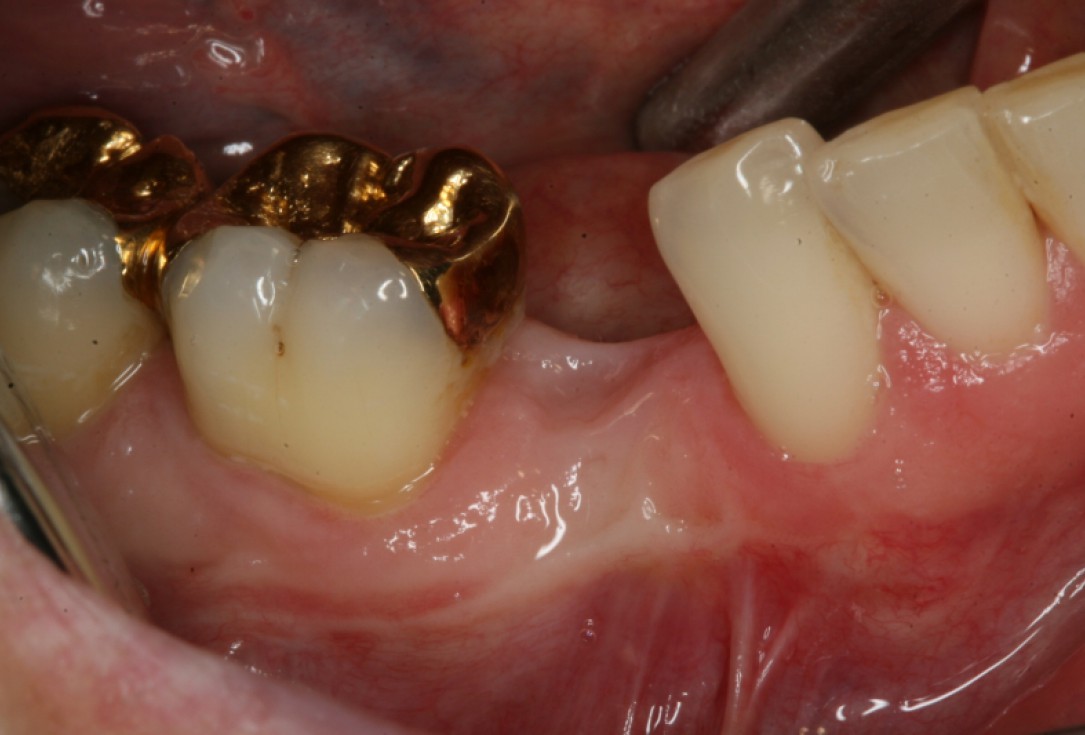

Initial situation: Inflammated tooth #12

Pre-surgical probing reveals a deep intrabony defect on the distal aspect of the upper canine.